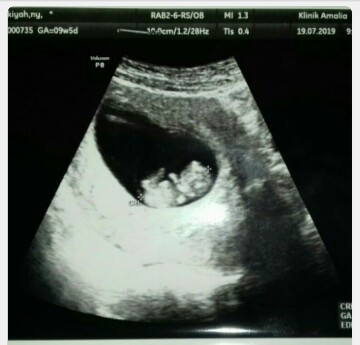

Ini bun. 9w5d